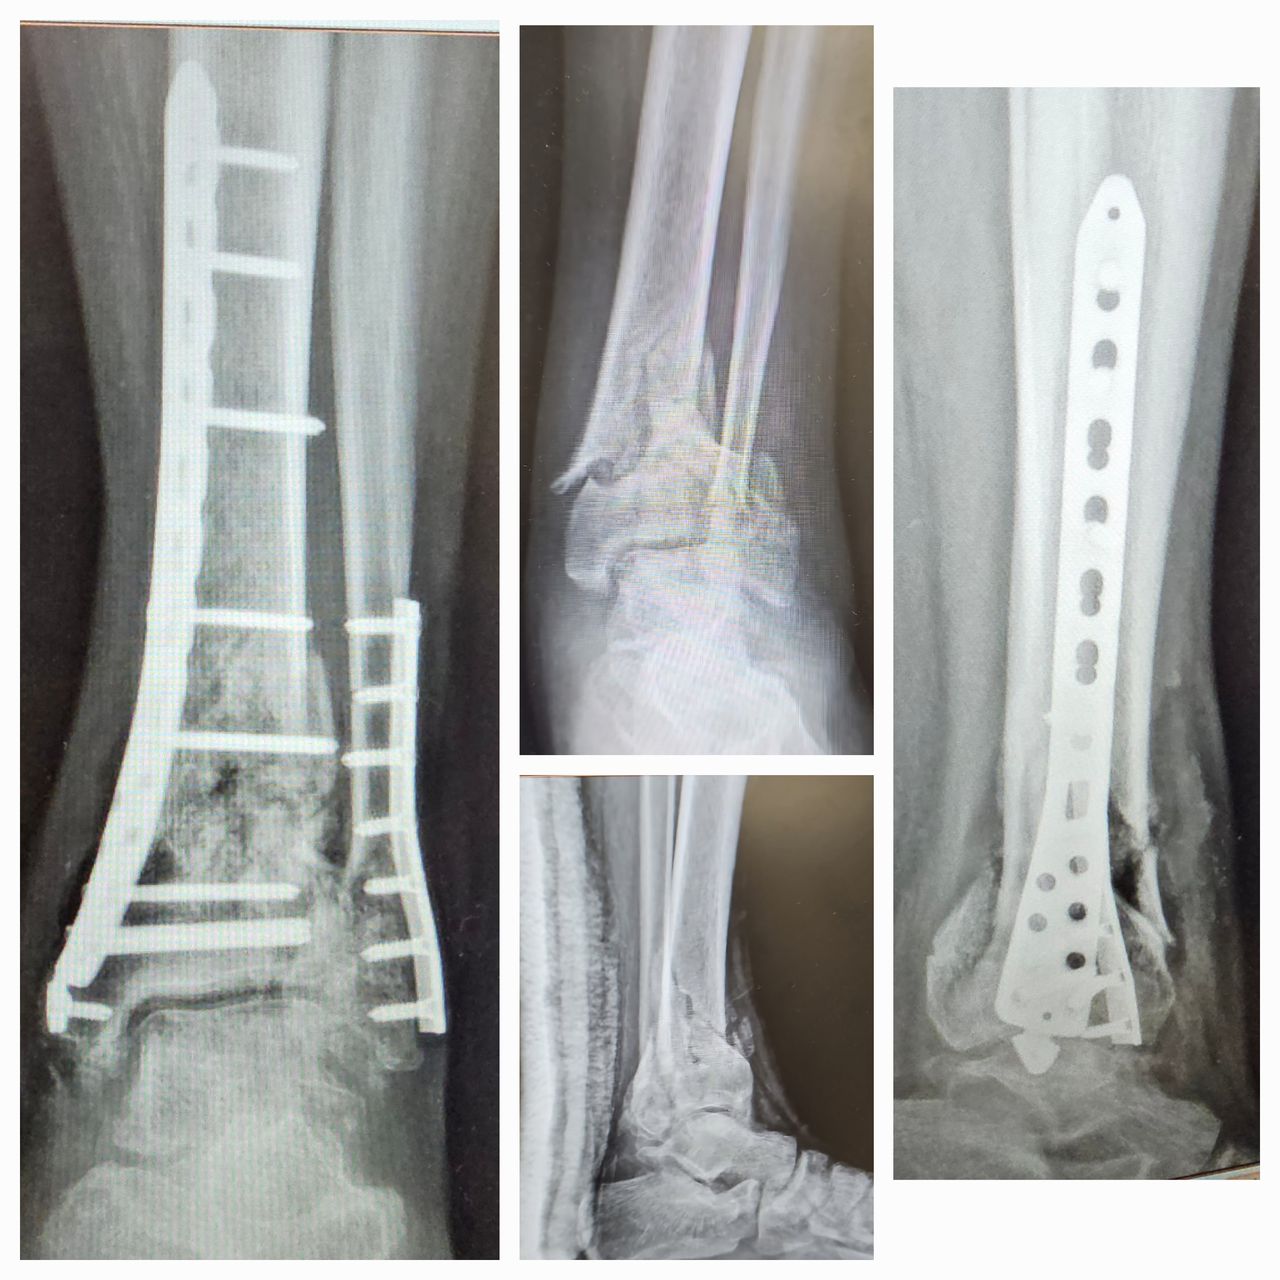

Fotos y videos